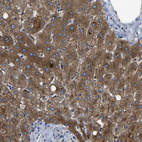

Immunohistochemical staining of human urinary bladder shows strong cytoplasmic positivity in urothelial cells.